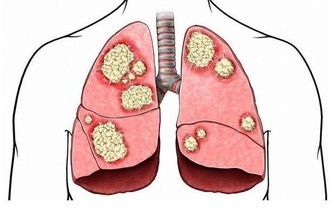

從腸道本身來看,如果持續腹瀉,還伴隨發燒、血便、體重減輕,有可能是炎症性腸病,如潰瘍性結腸炎、克羅恩病。這是兩種疾病,但都因為頻繁腹瀉,吸收差,會導致人非常虛弱。

大腸癌也會導致慢性腹瀉,但可能不全是腹瀉,也可能表現為腹瀉和便秘反復交替發生。

每天多喝水,適當多吃含植物纖維較多的食物,如新鮮蔬菜、水果。這不僅可以防止便秘,還能降低腸道惡性疾病(如結腸癌)的發生。